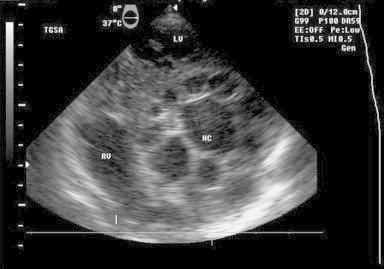

A 56-year-old woman living in rural area, presented with history of progressively increasing dyspnea for last one year. She was diagnosed as having pericardial effusion (PE) nine months back and had received anti tubercular treatment (ATT) for the same duration without any relief in symptoms, presuming the effusion to be tuberculous. Her chest X-ray revealed cardiomegaly. Routine investigations were normal with strongly positive hydatid serology (ELISA). Transthoracic echo window was suboptimal revealing only moderate PE. CT and MRI demonstrated multiple pericardial cysts and ruled out any other organ involvement. The intraoperative TEE examination confirmed the presence of pericardial cysts. Following midline sternotomy, after opening of pericardium and complete surgical evacuation of pericardial effusion and visible cysts, TEE examination revealed another transitional lesion – unilocular anechoic cystic lesion round in shape with a clearly visible cyst wall (laminated layer) and floating laminated membranes (water lily sign) in the transverse pericardial sinus (between aorta and pulmonary artery) Fig. 1. Doppler examination did not reveal any compression of the great arteries.

Fig. 1.

TEE image – mid esophageal right ventricle inflow outflow view: showing cystic lesion in transverse pericardial sinus – transitional cyst.